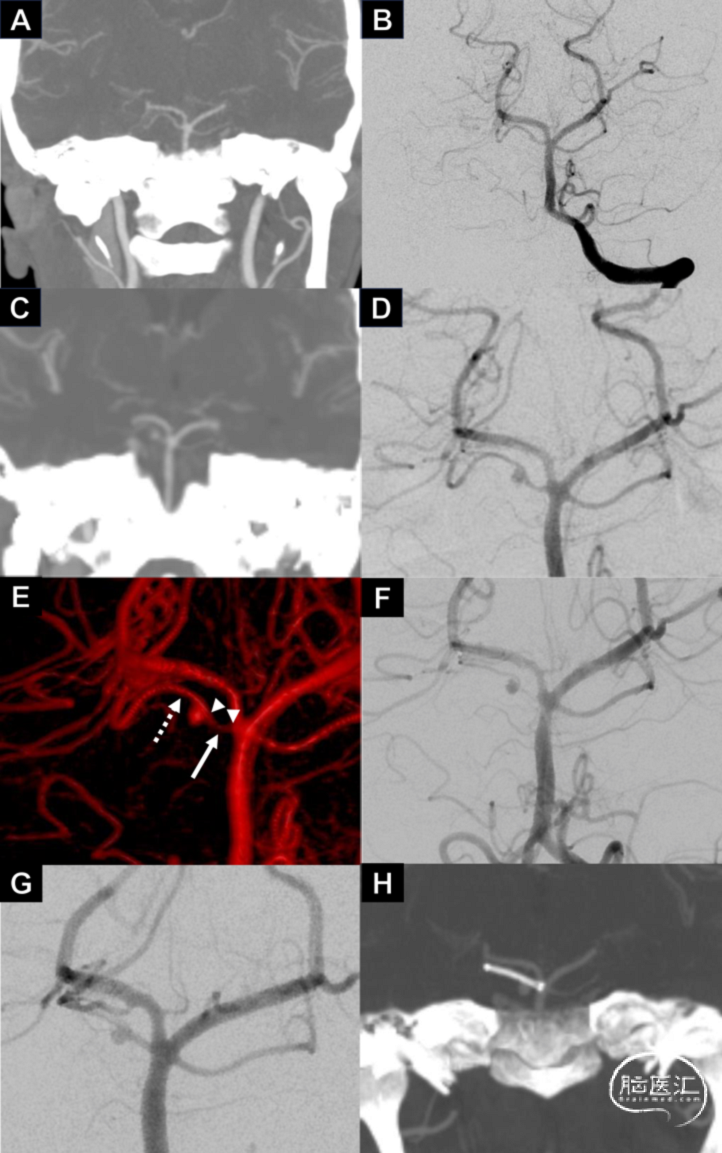

女性,40岁,以“运动后头痛数小时”为主诉入院。入院CT提示中脑周围蛛网膜下腔出血。CTA提示未见明显异常(图1.A)。发病第2天DSA提示右侧SAC远端稍异常,未见明显动脉瘤(图1.B)。发病第7天DSA提示右侧SAC远端一明显夹层假性动脉瘤(1.6*1.7mm,图1.C-D),因血管痉挛,SAC起始处直径未测出(图1.E-F)。经考虑,术者拟对责任动脉瘤行分期治疗,一期使用LVIS Jr稳定动脉瘤,二期再植入FRED Jr血流导向装置。

图1.右侧SAC远端假性动脉瘤,一期使用LVIS Jr治疗(详见病例介绍)。